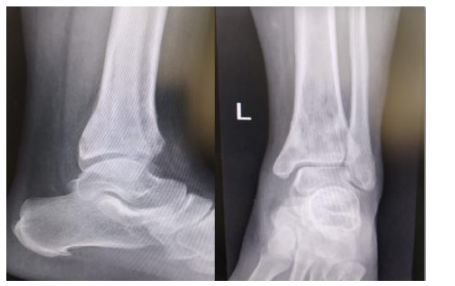

Patient was evaluated in our clinic, the radiograph showed the presence of distal tibial metaphyseal rarefaction and osteolytic lesion of about 2.5* 2.5 cm, there was no periosteal reaction or destruction and no soft tissue involvement (figure1). Blood parameters, bone profile and inflammatory markers were with in normal.

Figure 1: a radiograph of distal tibia showing an intramedullary osteolytic lesion 5-7 cm from tibiotalar articular magin with surrounding rarefaction with no obvious cortical distruction

Figure 1